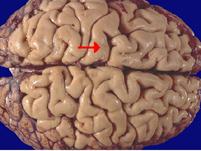

如图箭头所示为大脑哪个部位 ( )A、枕叶B、额叶C、中央后回D、旁中央小叶E、中央前回

问题 如图箭头所示为大脑哪个部位 ( )

选项 A、枕叶 B、额叶 C、中央后回 D、旁中央小叶 E、中央前回

答案 E